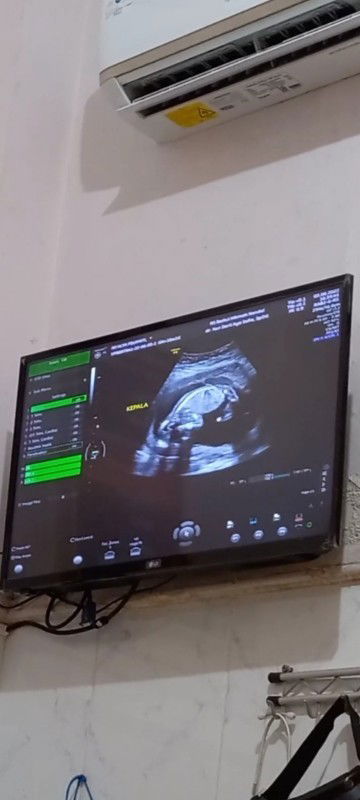

Janin 4 bulan lebih 2 hari ♡